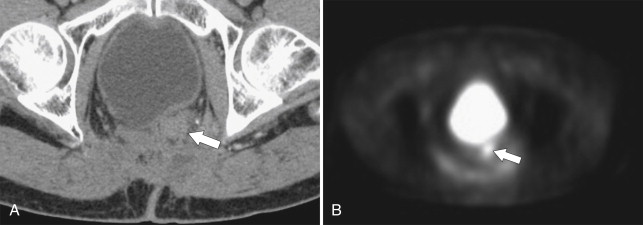

Ultrasound (US) sometimes shows a hypoechoic cystic mass with a thick wall, which has an echogenic outer layer and hypoechoic inner layer. On BE the cyst produces a mass effect of adjacent bowel and on CT appears as a nonenhancing mass, compressing or displacing the adjacent bowel, which may contain simple fluid, hemorrhage, or proteinaceous fluid ( Fig. 5-4 ). On MRI the enteric cysts are usually hyperintense on T2-weighted imaging, reflecting their cystic nature ( Fig. 5-5 ). Because many duplication cysts contain ectopic gastric mucosa, a Tc-99m pertechnetate radionuclide study can often show radionuclide uptake, which can also be observed within a Meckel diverticulum for the same reason.

Figure 5-4, Axial contrast-enhanced CT in a 46-year-old woman with a 4.5-cm homogeneous pararectal mass ( arrow ) caused by rectal enteric duplication.

Figure 5-5, Axial ( A ) and sagittal ( B ) T2-weighted imaging in a 30-year-old woman with a cystic 4.5-cm mass ( arrows ) in a posterolateral perirectal location resulting from a rectal duplication cyst.